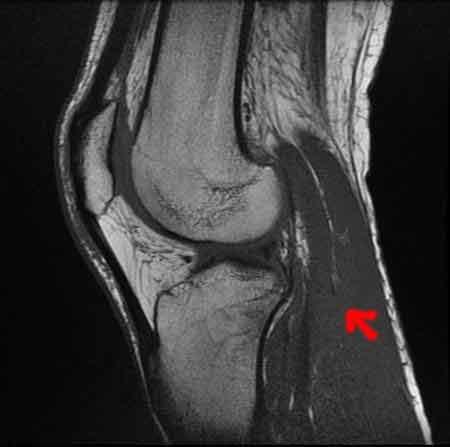

CONTRE RENDU IRM :

RUPTURE DU LIGAMENT CROISE ANTERO-EXTERNE.![]()

(le fameux.....)

FISSURATION VERTICALE DE GRADE 3 ASSOCIEE A LA POSTERIEUR DU MENISQUE.![]()

dc intervention chirurgicale en vue.......dc en gros c'est, 45MN d' operation, et pas de foot avt 4 mois a partir de la date d' operation ( si tout va bien bien sur...) et une putain de reeducation de la mort....WOUèèèèGROOOO

bon apres un pti tour a l hopital St Louis, une batterie de tests et de radios, RIEN DE CASSé, les ligaments ont l' air OK. c' est les menisques qui en ont pris un pti coup...donc IRM samedi. en attendant, attelle de la jambe pendant 2 semaines. a suivre....